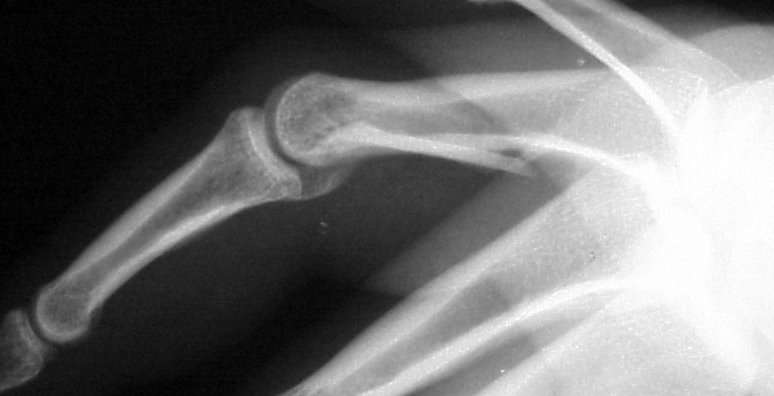

Xrays show a complex intraarticular fracture of the proximal phalanx head. There is a displaced spiral oblique longitudinal fracture with a second oblique coronal split through the articular surface of the radial condyle.

Palmar displacement of a portion of one condyle is visible on the lateral view.